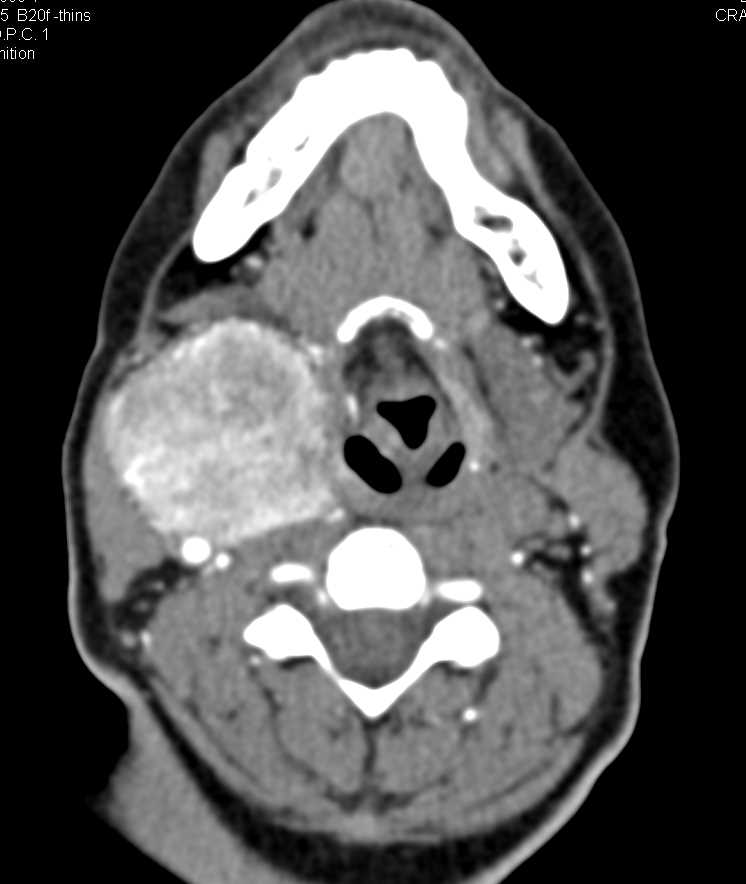

Редкое заболевание на снимках: фотографии параганглиомы забрюшинного пространства